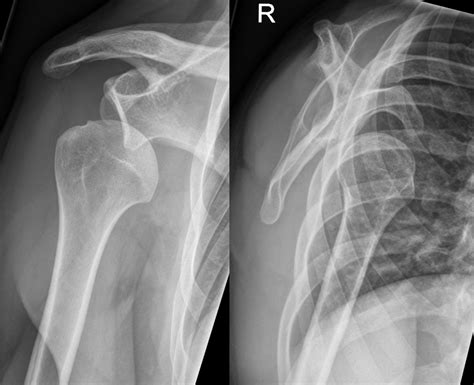

Following the confirmation provided by the Dislocated Shoulder X Ray, the medical team will proceed with reduction. Once the shoulder is back in its proper position, the doctor will often order a post-reduction X-ray. This second round of imaging is vital to confirm that the bone is correctly seated and that no new fractures were created during the reduction procedure.

• Assessing alignment: It helps doctors identify the specific type of dislocation—whether it is anterior (forward), posterior (backward), or inferior (downward).

Typically, the technician will request at least two or three different views of the shoulder to ensure a comprehensive diagnosis:

• Axillary View: This view captures the shoulder from underneath, which is crucial for identifying if the bone has moved forward or backward.

• Scapular Y View: This provides a lateral perspective, allowing the radiologist to see if the humeral head is centered in the socket of the scapula.